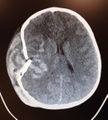

Skull fracture (peds)

- All skull fracture require Head CT